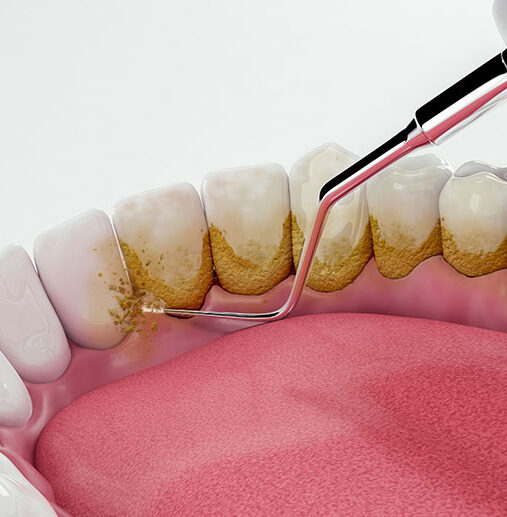

Diş Taşı Temizliği

Diş Taşı Temizliği Beslenme alışkanlığı, tükürük kalitesi, sigara kullanımı, dişlerin birbirleriyle olan kontakları